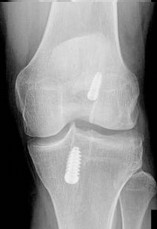

A 16-year-old female undergoes medial patellofemoral ligament (MPFL) reconstruction for recurrent patellar instability. Intraoperative fluoroscopy is used to determine the anatomic femoral attachment site (Schöttle's point). Which of the following radiographic landmarks correctly identifies this location on a strict lateral radiograph?

Schöttle's point is the radiographic landmark for the femoral origin of the MPFL. On a strict lateral radiograph, it is found 1 mm anterior to a line extending from the posterior femoral cortex, 2.5 mm distal to the posterior articular border of the medial femoral condyle, and proximal to the posterior projection of Blumensaat's line.